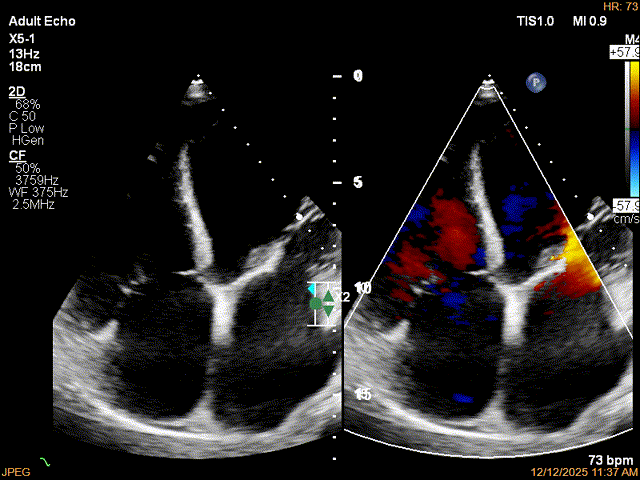

为了避免长时间TEE对食道造成损伤,术前即刻3D-TEE短时进一步明确二尖瓣病变相关解剖情况。

术前Bi-com

术前3D

术前3Dcolor

3D-TEE二尖瓣相关解剖学参数:后叶长度:22-25mm,前叶长度:31-34mm;瓣环AP径:47mm,ML径:48mm;瓣口面积:约7.8cm²;脱垂宽度:30mm,最大连枷间距:14mm。

四条肺静脉均可测及收缩期反向血流

术前即刻TEE进一步明确了二尖瓣反流的机制(DMR)及反流程度(5+),重点完善了病变区域二尖瓣解剖结构的评估,预估手术难点/影响手术效果的解剖结构为冗长的二尖瓣后叶(PML约25mm),宽大的脱垂(Flail Width约30mm),超大的连枷间距(Flail gap约14mm)。